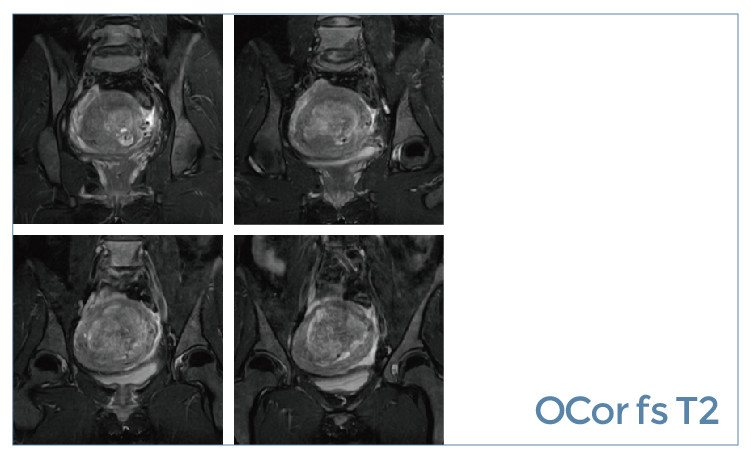

【朗润影像档案】20190621磁共振影像病例结果讨论